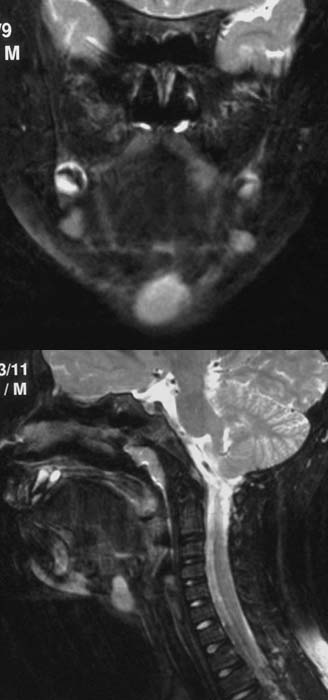

In

der T2-Wichtung kommt im coronaren Schnittbild (linkes Bild) eine signalreiche

etwas unscharfe Raumforderung zur Darstellung.

Im sagittalen Schnitt in T2-Wichtung etwa in der Medianebene (rechtes Bild)

kommt diese Raumforderung ebenfalls signalreich

zur Darstellung.